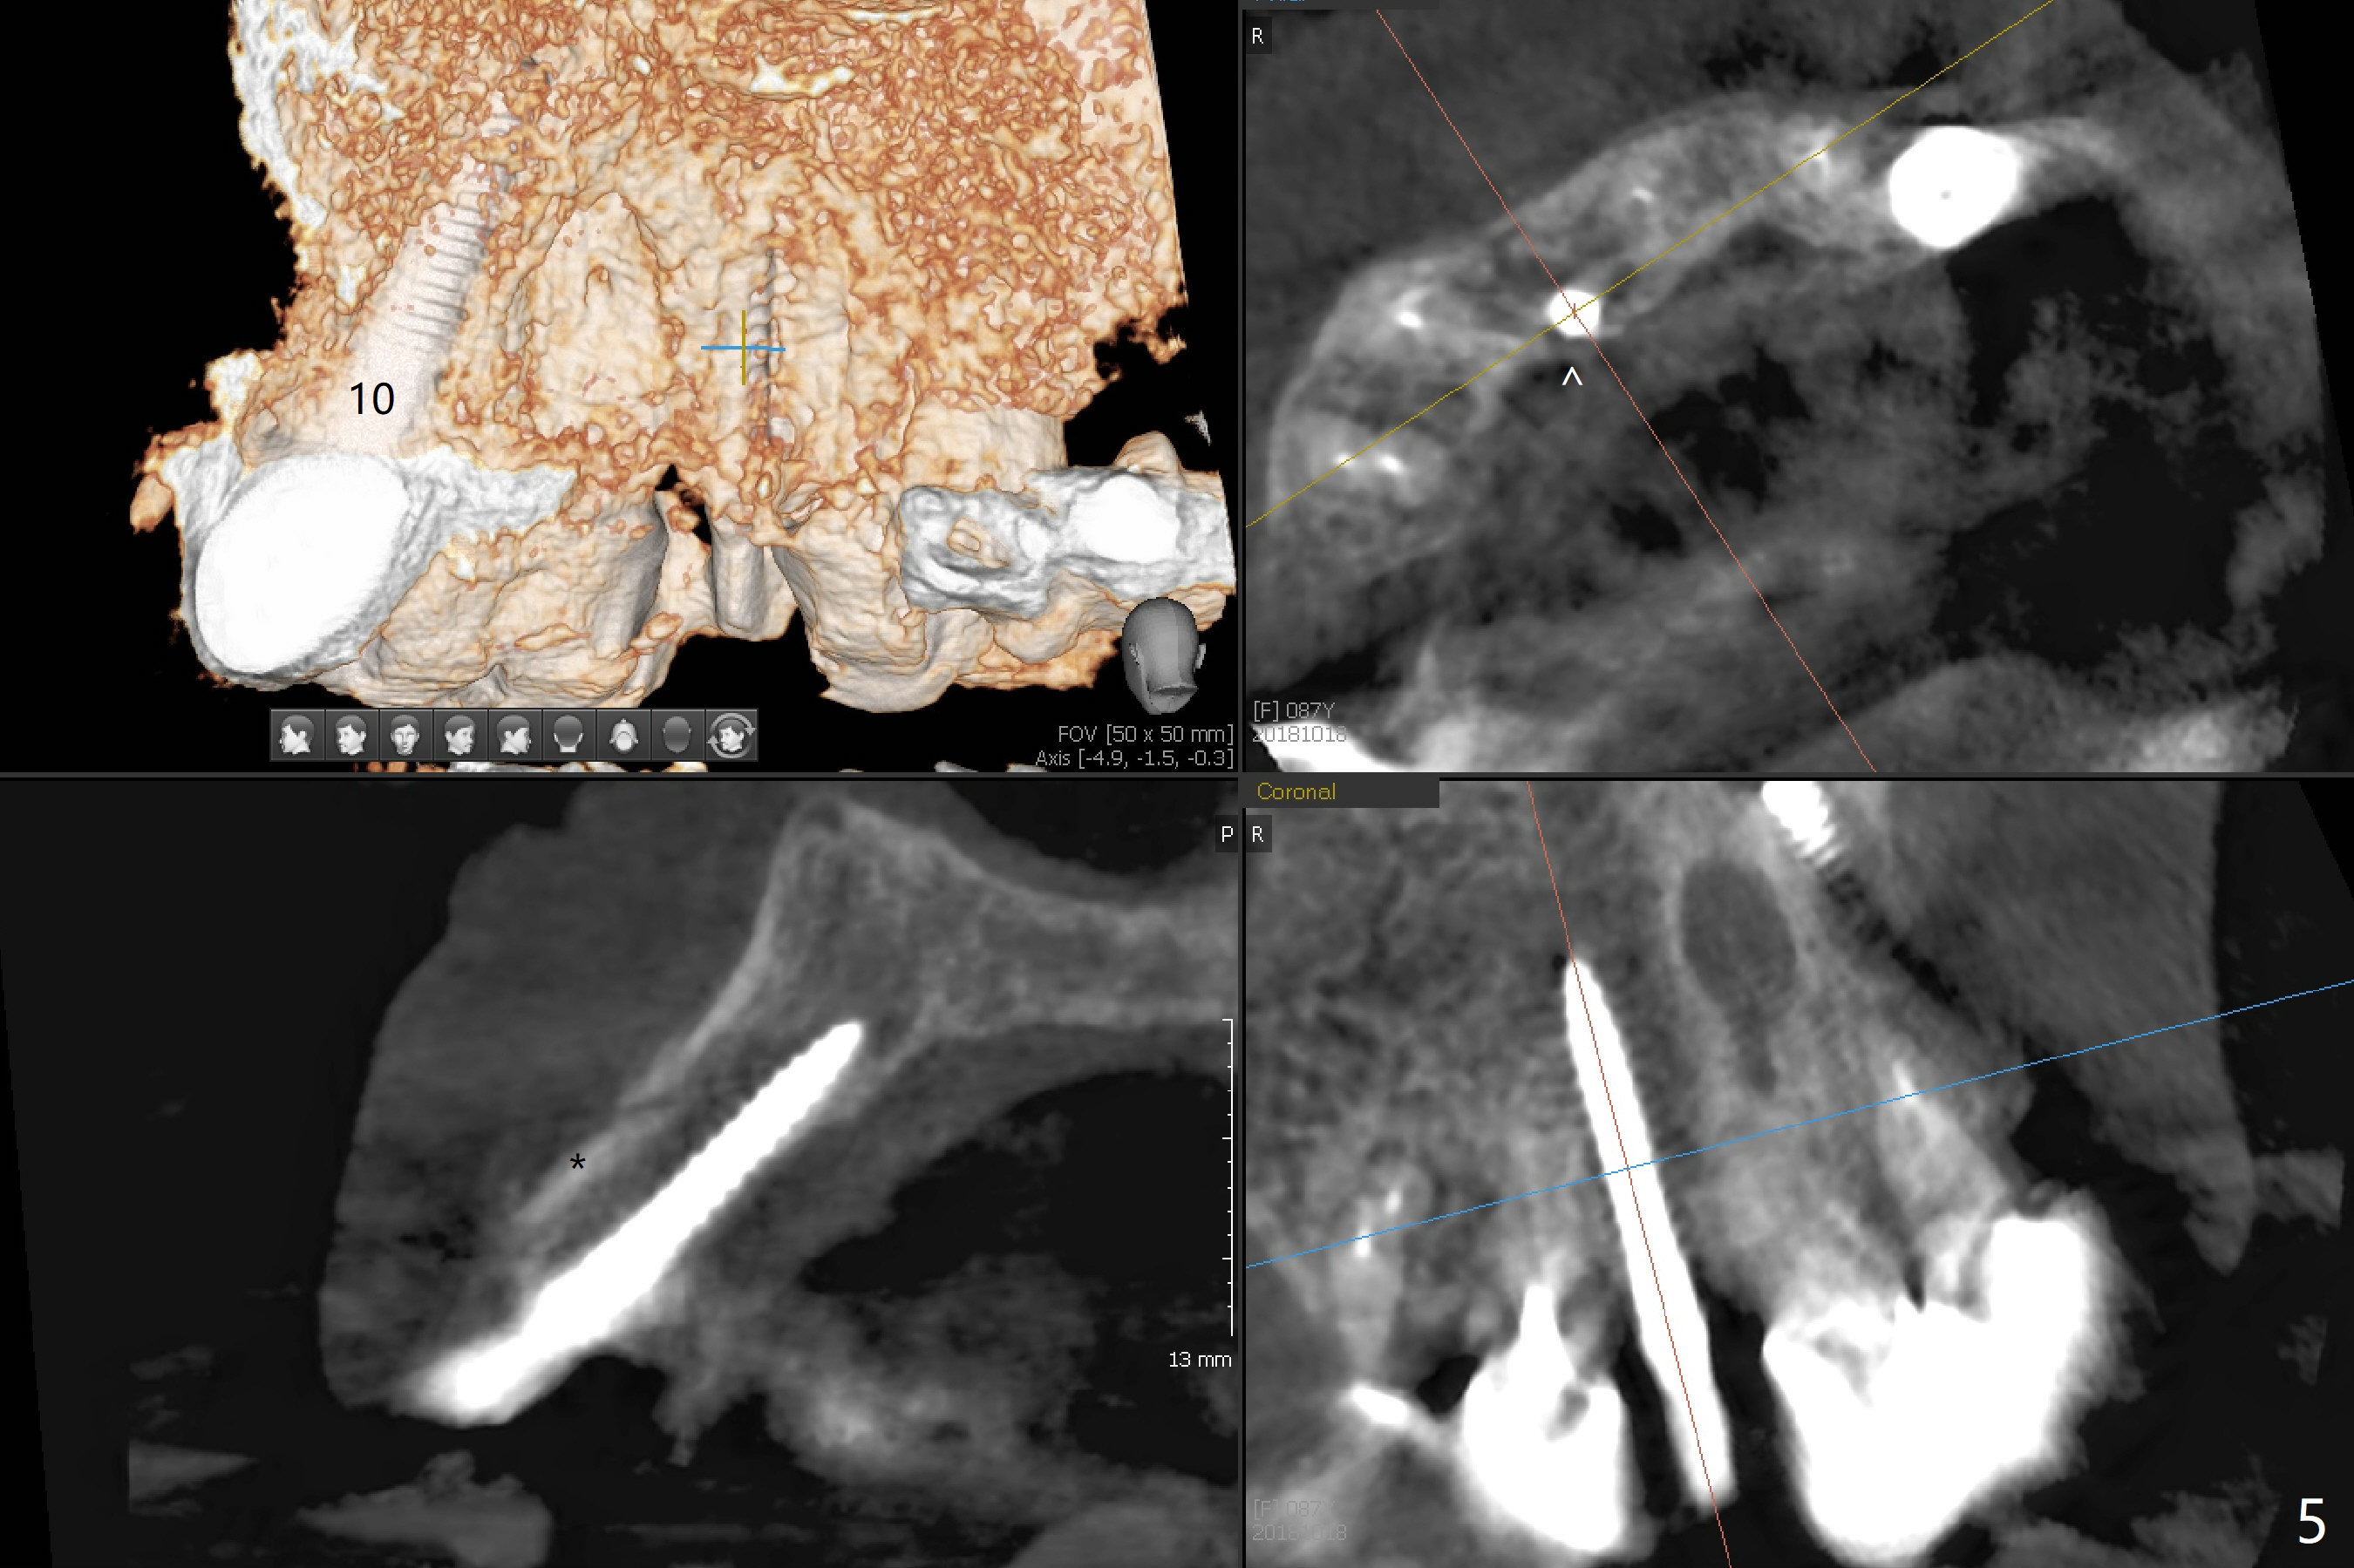

The edentulous area at #7 is narrow both buccopalatally and mesiodistally, whereas the crowns of the neighboring teeth are long (Fig.1,2). For the latter reason, it is difficult to remove the apical portion of the root, including gutta percha with surgical handpiece (Fig.3 *) for socket shield (Fig.2 *). To avoid the perspective implant touching socket shield, initial osteotomy is palatal. When a 2 mm drill is being used, the coronal end of the palatal plate starts to perforate. A 2.5x14 mm 1-piece implant is placed with 30 Ncm (Fig.4). The palatal plate is thin (Fig.5). Preop CT will help determine the position of initial osteotomy. The buccal gingiva seems to have been re-attached to the underlying alveolus and the provisional 1 month postop (Fig.6). The teeth #8 and 9 fracture (an implant is placed at #8 and bone graft at #9, while the implant at #7 is osteointegrating (Fig.7). In fact the shield is exposed without symptom. A year postop, another dental provider sends a photo of apparently hemorrhagic gingiva around #7 crown (Fig.8). A few days later with oral hygiene instruction, the gingiva around the exposed root piece is healthy (Fig.9). The root surface is reduced; with socket shield, there is no buccal plate collapse; in contrast the neighboring buccal plate (at #8 and 9) is concave (Fig.10). There is minimal exposure 11 days postop (Fig.11). The gingiva palatal to the shield is erythematous, a possible sign of periimplantitis. The socket shield at #7 appears to be fused with the buccal plate 11 months postop (Fig.12), as compared to the implant at #10 nearly 4 years postop (Fig.14). The buccopalatal widths at #7 and 10 are equivalent (Fig.13,15).